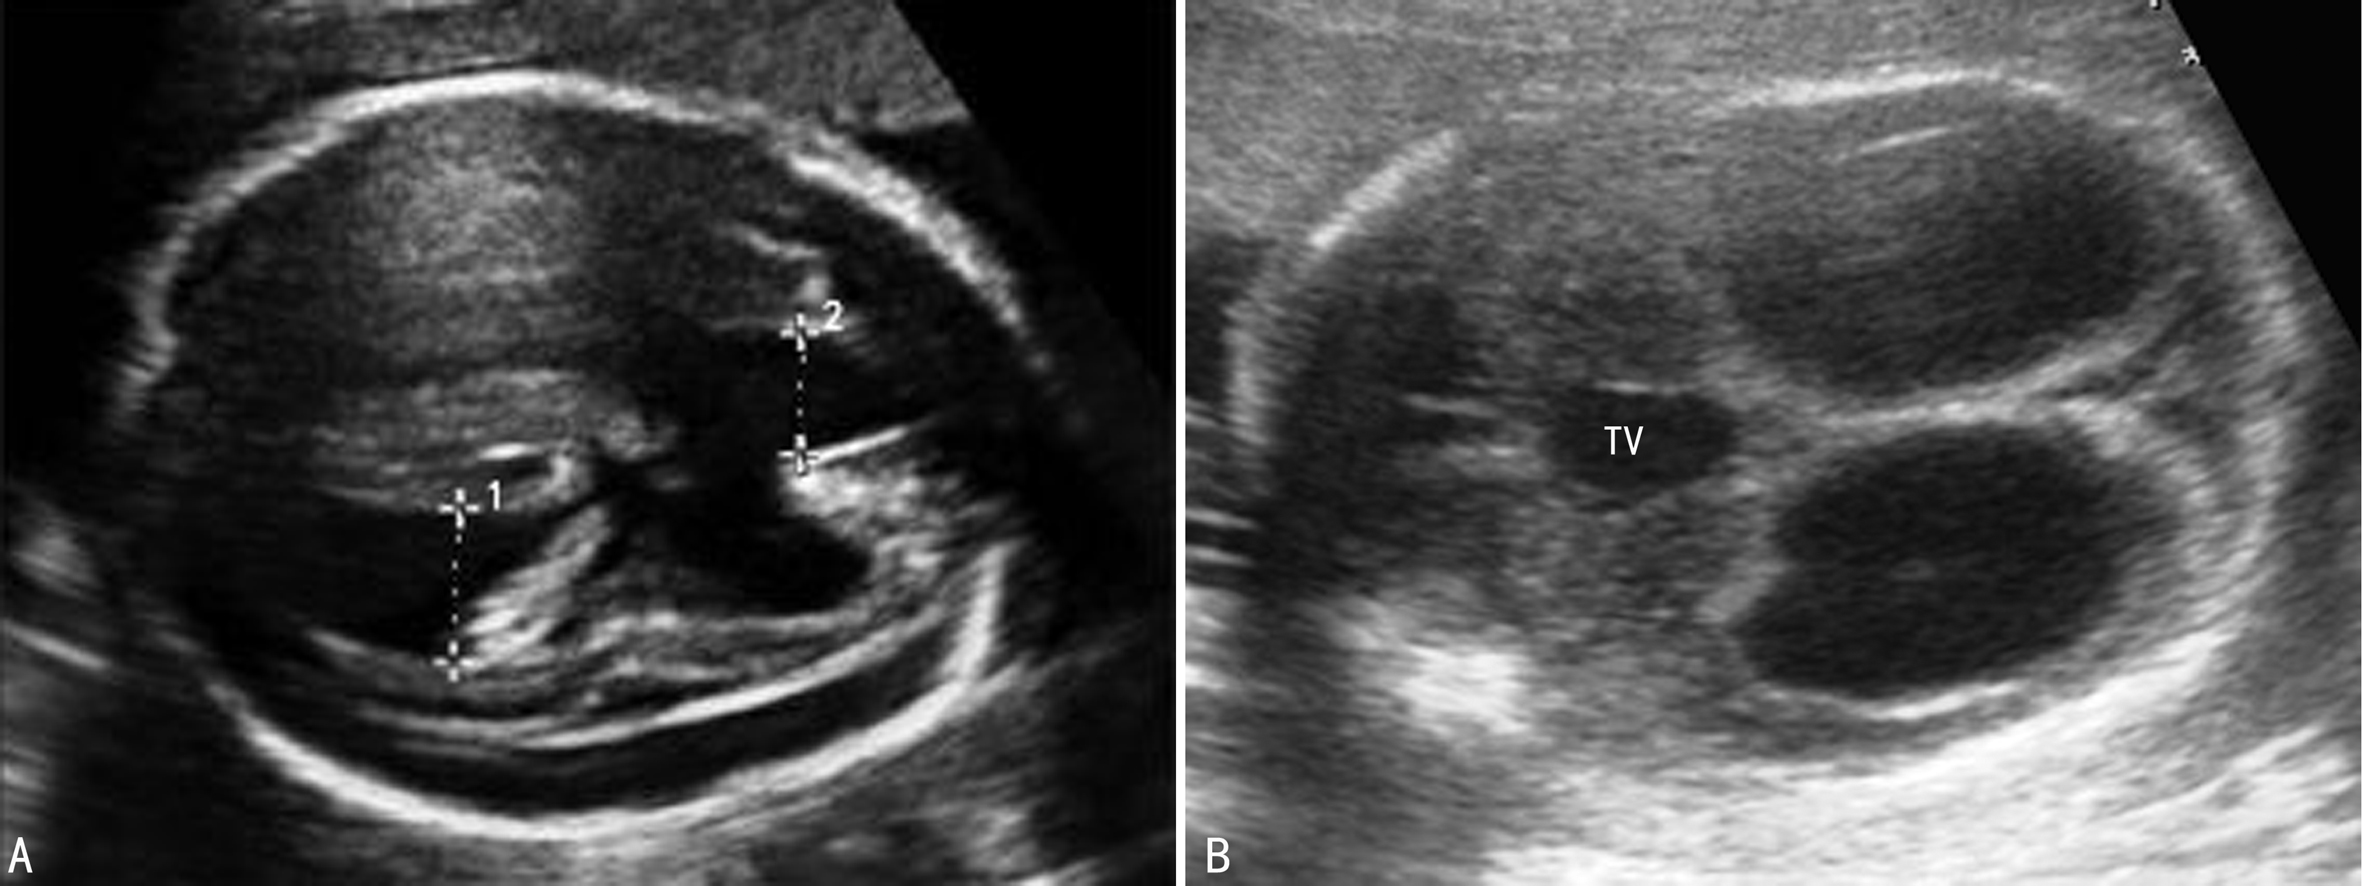

(1)单纯性脑室扩张(IMVM):可以是单侧或双侧(图1),3%~15%有染色体异常,通常为非整倍体异常,主要见于21-三体,在13-三体和18-三体中也常见,还可见于47XXY、47XYY、三倍体、染色体部分缺失、非平衡易位等。大多数IMVM可以自行缩小至正常范围,尤其是侧脑室宽度<13mm时自行消失的可能性很大,与CSF引流暂时性失调有关。McKechnie等报道有83%的轻型脑室扩张患儿可以正常发育,但困扰医生做出抉择或进一步检查的是有14%的IMVM会加重。因此,超声检查显示IMVM后仍需要进行系统的胎儿检查,仔细辨认有无伴发的其他异常、有无染色体异常的其他软指标。如果没有发现其他异常并且IMVM在分娩前消失的则有90%的胎儿预后良好,双侧不对称的IMVM(宽度差异>2mm)时预后不良,约一半的胎儿出生后有神经系统发育异常。侧脑室内径在10~12mm的预后优于内径13~15mm的胎儿。

图1胎儿双侧侧脑室扩张(TV第三脑室)